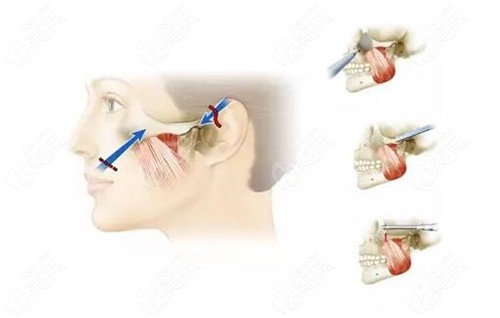

潘宝华颧骨内推如何?技术好、经历也丰富,潘宝华医生颧骨内推手术研发的“微创颧骨颧弓降低术”,承袭了日式自然协调的塑型风,手术主打的:微创、自然、不下垂。

①手术会从口内切开,尽有一个切口,大大降低留疤概率,避免出现手术痕迹明显等问题;

②同时,对颧骨两端截断,微创的方式做颧骨内推半折断固定,钛钉钛板固定,术后不容易有断层感;

③加上潘宝华颧骨内推还会做软组织提拉复位,降低术后下垂/松弛等问题,面部紧致,不容易显老。